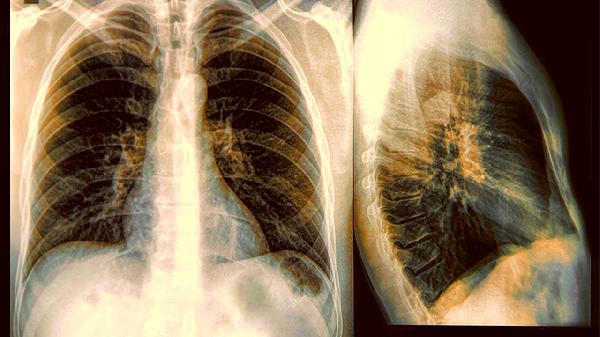

肺部结节8毫米属于中等大小结节,通常需要结合影像学特征和患者病史综合评估。良性结节多表现为边缘光滑、钙化明显,常见于肺部感染后遗留的瘢痕、结核球或错构瘤。这类结节生长缓慢,建议每6-12个月进行低剂量CT复查,观察结节变化情况。若结节在随访期间保持稳定,可延长复查间隔。对于存在炎症表现的结节,医生可能开具抗生素如左氧氟沙星片、阿莫西林克拉维酸钾片进行试验性治疗。

当结节呈现分叶状、毛刺征等恶性征象,或随访中体积增大超过2毫米时,需警惕肺癌可能。此时建议进行PET-CT检查或经皮肺穿刺活检明确性质。确诊为恶性的8毫米结节属于早期肺癌,可通过胸腔镜下肺段切除术或楔形切除术治疗,术后5年生存率较高。对于无法耐受手术的高龄患者,可考虑立体定向放射治疗。部分特殊感染如隐球菌病、曲霉菌病也可能形成8毫米结节,需通过病原学检查确诊后针对性使用抗真菌药物如氟康唑胶囊、伊曲康唑胶囊。